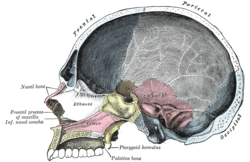

![]() Position of parietal bone (shown in green) | |

Position of parietal bone (shown in green). Animation.

Cranial bones